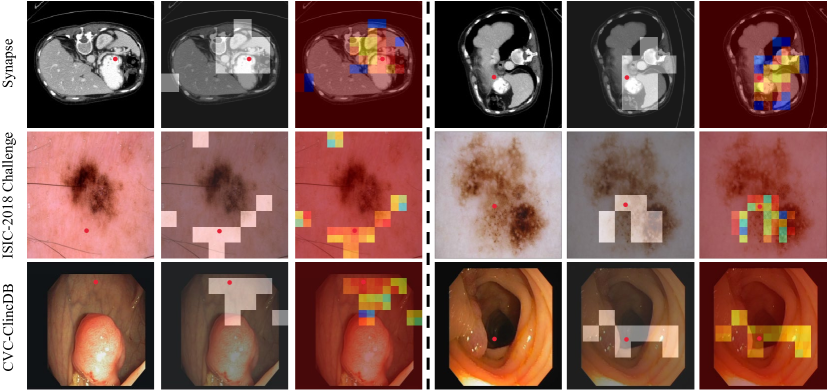

In this work, we show that the dynamic and query-aware sparse attention is effective on both reducing computational complexity and improving model performance. To further illustrate how the sparse attention works on medical image segmentation task, following [24], we visualize routed regions and attention response w.r.t. query tokens. We adopt routing indices and attention scores, which are extracted from the final block of the 3rdsuperscript3𝑟𝑑3^{rd} stage in the encoder, for this visualization. That is, these values are obtained from the feature map of H16×W16𝐻16𝑊16\frac{H}{{16}}\times\frac{W}{{16}} resolution, while the visualizations are presented in the images of original resolution. The results on Synapse multi-organ segmentation, ISIC-2018 Challenge, and CVC-ClinicDB datasets are shown in Fig. 6. One can clearly see that the type of sparse attention can effectively find semantically most related regions, which indicates the dynamic sparse attention computation mechanism is effective for the calculation and selection of sparse patterns of medical images. However, exploring other efficient sparse pattern computation methods are still necessary, and also the focus of our future work.

Refer to caption

Figure 6: Similar to [24], visualization of attention maps on three datasets. For each dataset, we visualize a query position on the input image (left), corresponding routed regions (middle), and a final attention heatmap (right).